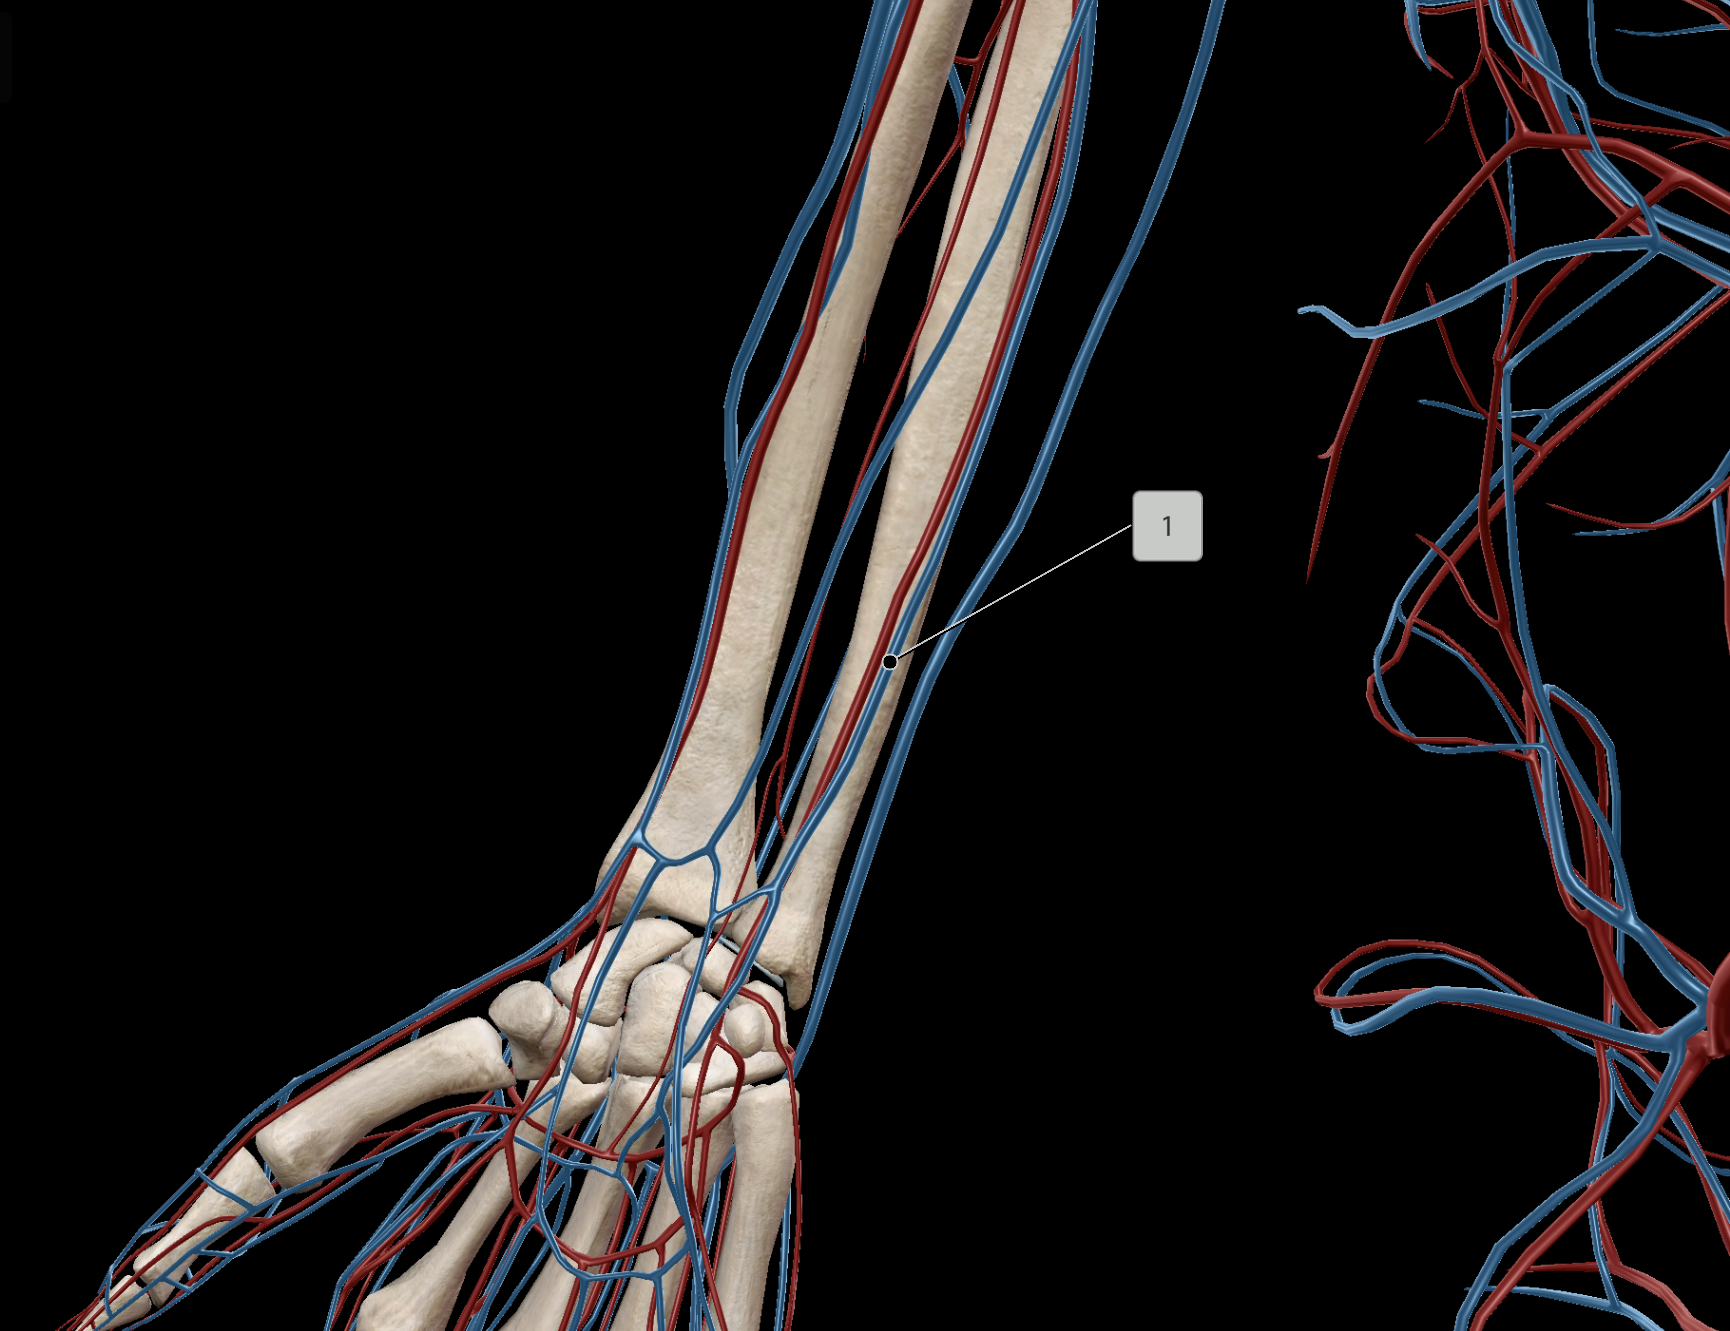

Radial Vein

Ulnar Vein

Ulnar Artery

Radial Artery

Median Cubital Vein